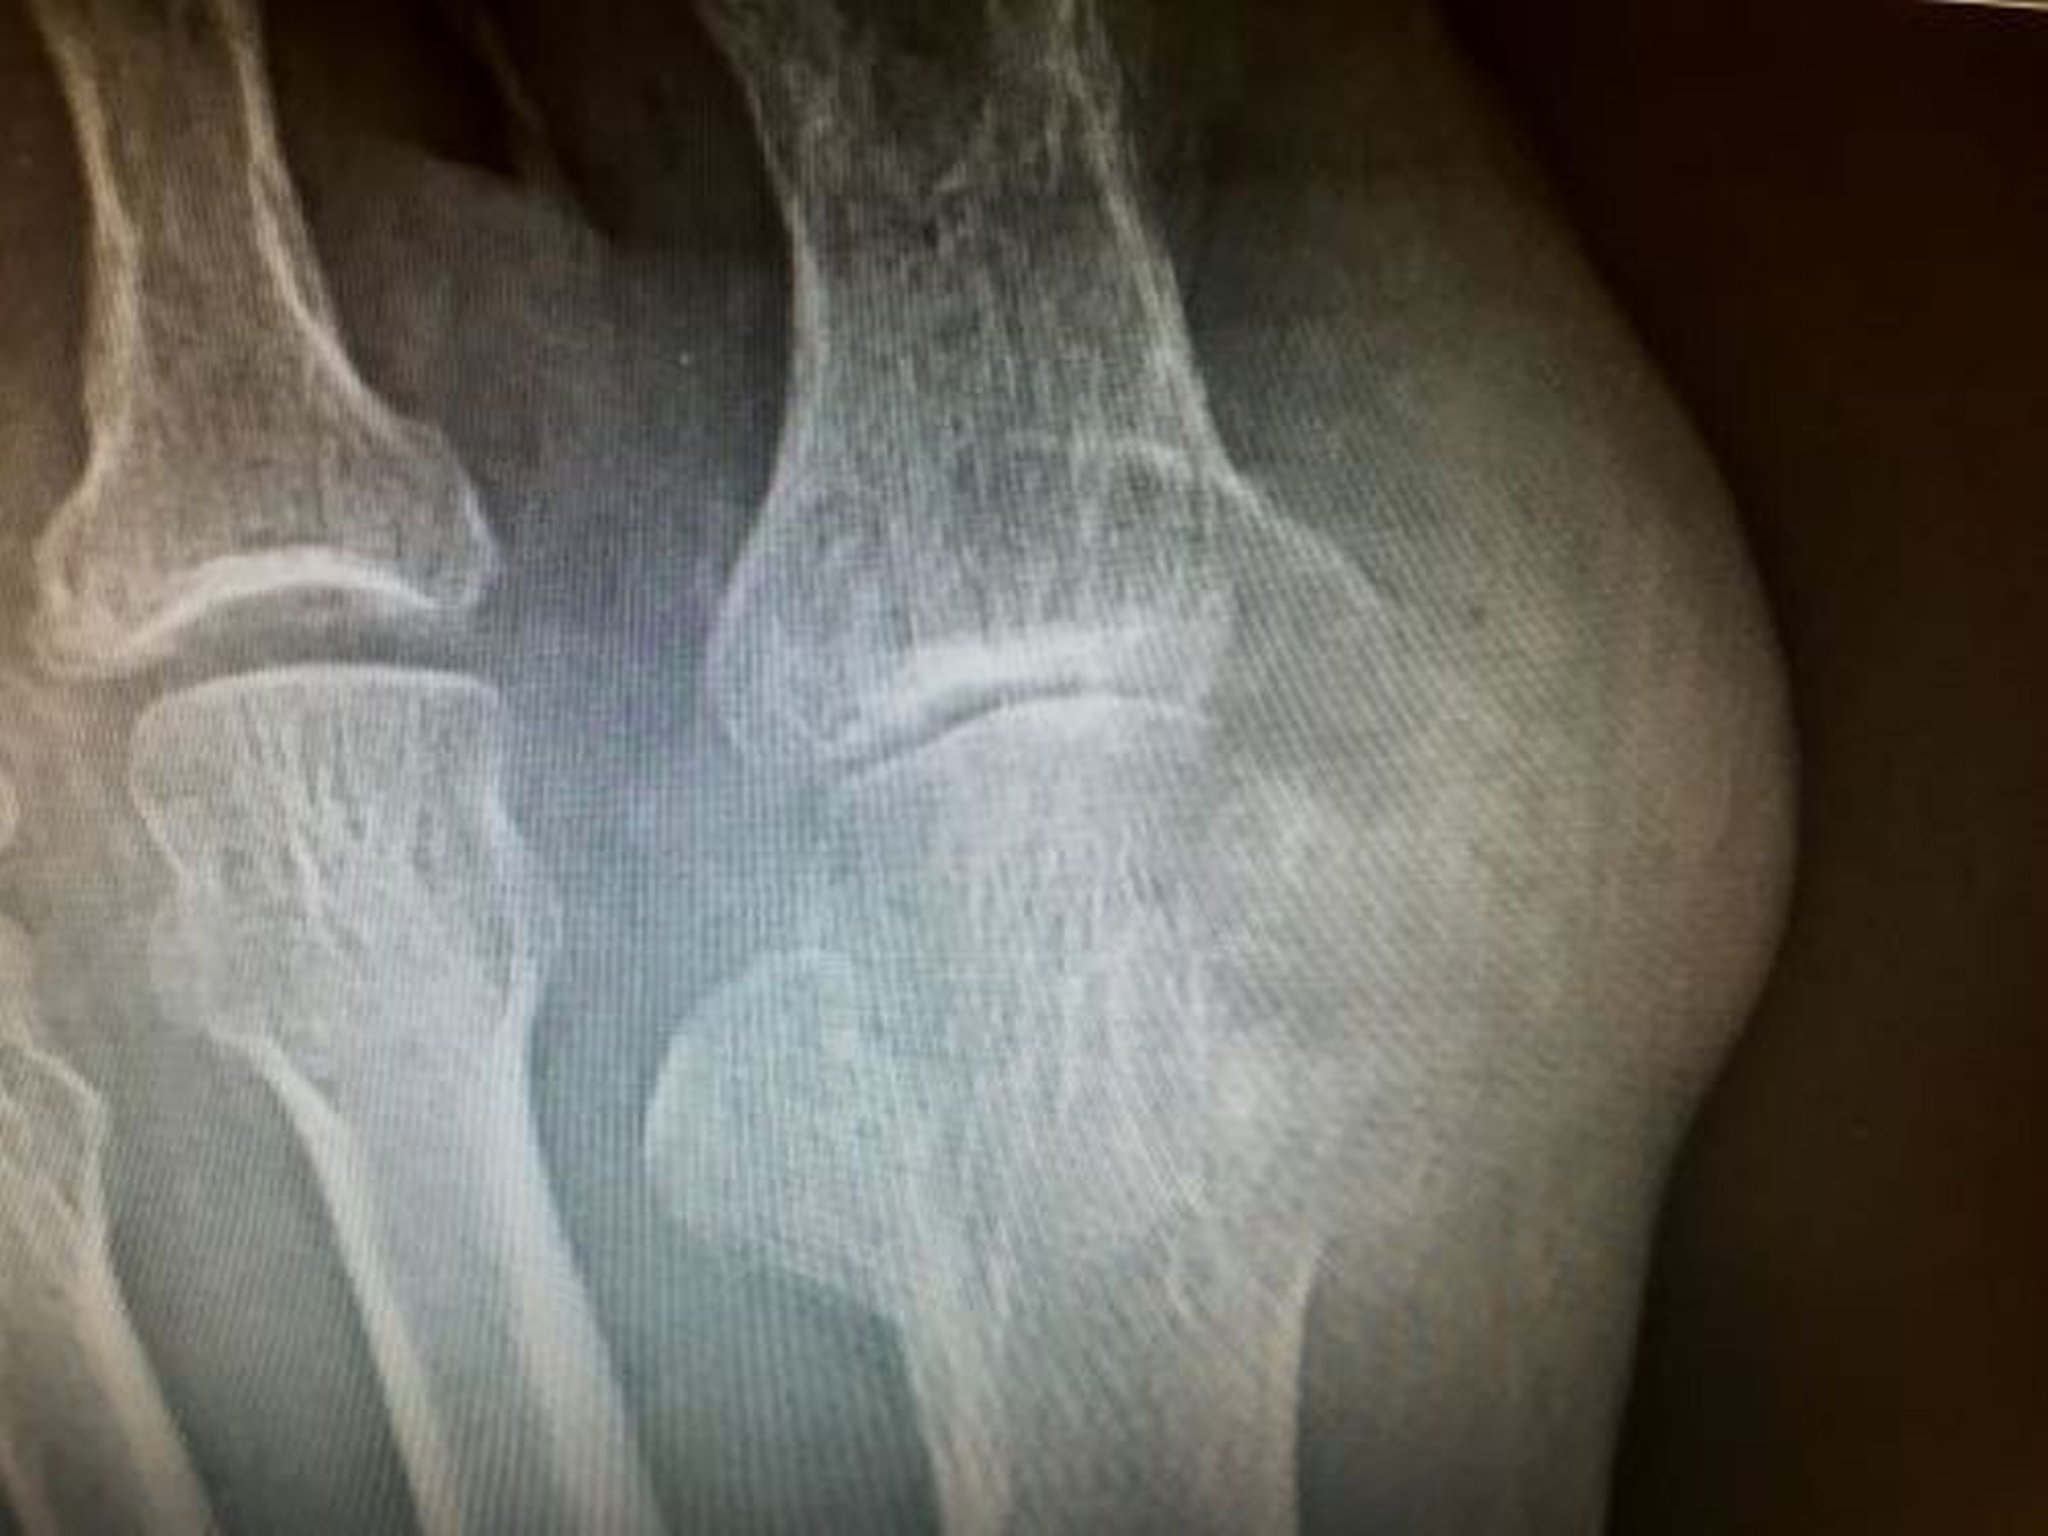

Tofos com erosão

Esta foto mostra grandes erosões causadas pelos tofos envolvendo o osso metatarsal distal e na falange proximal do hálux.

Imagem cedida por cortesia de N. Lawrence Edwards, MD.